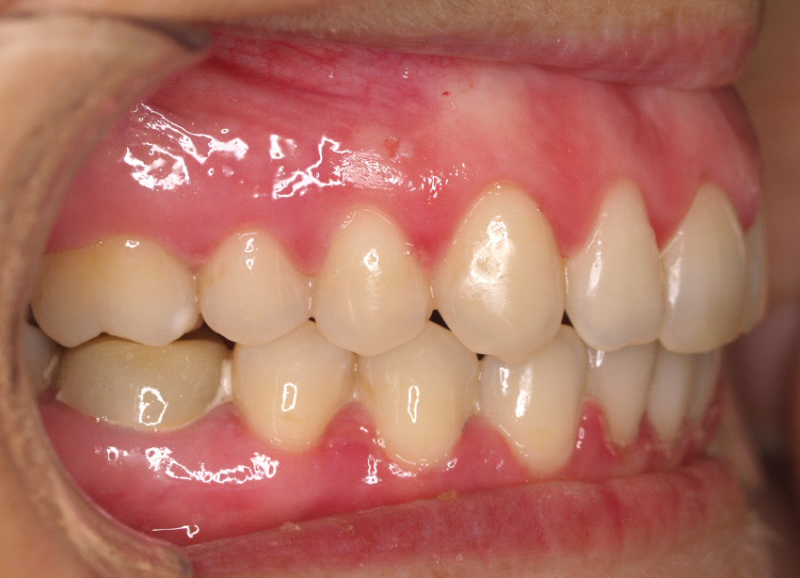

Premolar mandibular incluido + fenestración

45 incluido

Radiografía de final de tratamiento